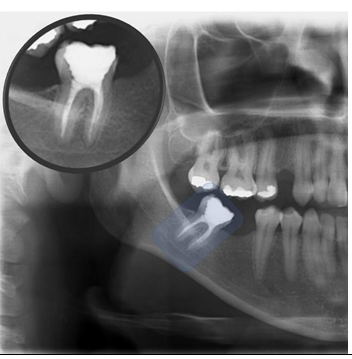

Figure 9 Panoramic X-ray cutout showing highlighted tooth 48, with some mesiangulation. Note that in iatrogenic endodontic treatment of the mesial root, one of the root canals is partially filled. This may be causing the space in the apical periodontal ligament to increase in that root .

Figure 10 Panoramic X-ray cutout showing highlighted tooth 46, with correct endodontic treatment and with a coarse excess on its mesial surface, that causes iatrogeny. As the tooth is dead, the patient will be slow to feel the symptoms of this iatrogeny, excess restoration, which will possibly destroy the tooth. Note that there is already a caries infiltration.

Figure 11 Panoramic X-ray cutout showing highlighted tooth 46, with iatrogenic endodontic treatment. There is a prosthetic crown with a fused metallic core with a larger support at the distal root. Note that in endodontic treatment there is a lack of material in both roots, and apical radiolucent images of these, partially diffuse, greater in the mesial root, compatible with apical lesion such as chronic abscess or granuloma. Both have a slow characteristic, due to the halo, or condensing osteitis that has formed around the lesions. Tooth 45 also has an endodontic treatment, but it is correct.

Figure 12 Periapical radiographic images of the premolars and left molars, where we point with the red arrows, the resorption of the alveolar bone crest between teeth 25-26, due to the lack of contact point between these teeth, exacerbated by the lack of contour of the teeth. restorations in the respective proximal boxes. This iatrogenesis is causing the periodontal problem.